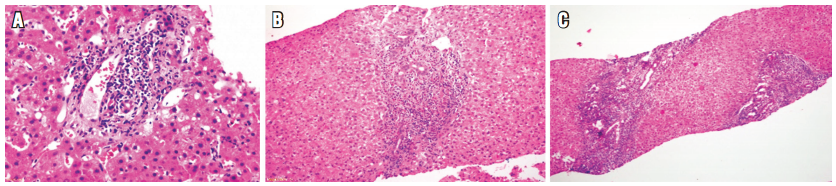

En el examen anatomopatológico, en las fases más iniciales, los cambios son inespecíficos, semejan lo observado en la lesión de preservación con balonización de hepatocitos y necrosis hepatocitaria en zona 3. El endotelio es la célula directamente lesionada; por lo tanto, el daño microvascular que se produce en las primeras horas lleva a hemorragia focal con agregados sinusoidales de células inflamatorias de tipo polimorfonucleares neutrófilos y plaquetas, con trombosis de vasos pequeños. Progresa a edema portal y periportal con reacción ductular o proliferación colangiolar, lo que semeja obstrucción de la vía biliar, con hipertrofia de células endoteliales que compromete vasos venosos portales y capilares, acompañado de linfocitos y eosinófilos adheridos al endotelio (Figura 3).

En casos severos puede existir trombosis de las ramas intrahepáticas de la vena portal, con infartos venosos y cambios extensos de tipo isquémico y formación de infartos geográficos; puede haber compromiso de venas y arterias hepáticas o de la vena cava inferior. Para este diagnóstico es indispensable asegurarse de excluir trombosis de la arteria hepática o la obstrucción biliar. Reactividad para C4d por inmunohistoquímica (en tejido incluido en parafina) es difícil de interpretar aisladamente; tiene varios patrones, debe ser intensa en al menos el 50% de las venas portales, en capilares del estroma portal o con distribución sinusoidal (Figura 4). Si existe disponibilidad de tejido en fresco o congelado, el método considerado más confiable son estudios de inmunofluorescencia con reactividad sinusoidal para C4d. También se ha demostrado reactividad linear para IGG o IGM, fracciones del complemento C3, C4, C1q, fibrinógeno en la pared de los vasos arteriales y presencia de anticuerpos anti HLA (17,20,21,22,23,24). Es importante enfatizar que se ha descrito presencia focal de C4d en una gran cantidad de aloinjertos, sin evidencia de rechazo humoral mediado por anticuerpos. Por lo tanto, el diagnóstico preciso de rechazo humoral puede ser útil para determinar e indicar la posibilidad del uso de plasmaféresis en el postoperatorio inmediato o mediato, y para evaluar en los protocolos actuales la posibilidad de trasplante ABO incompatible (24).